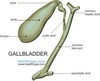

GB anatomy image

anatomic variants